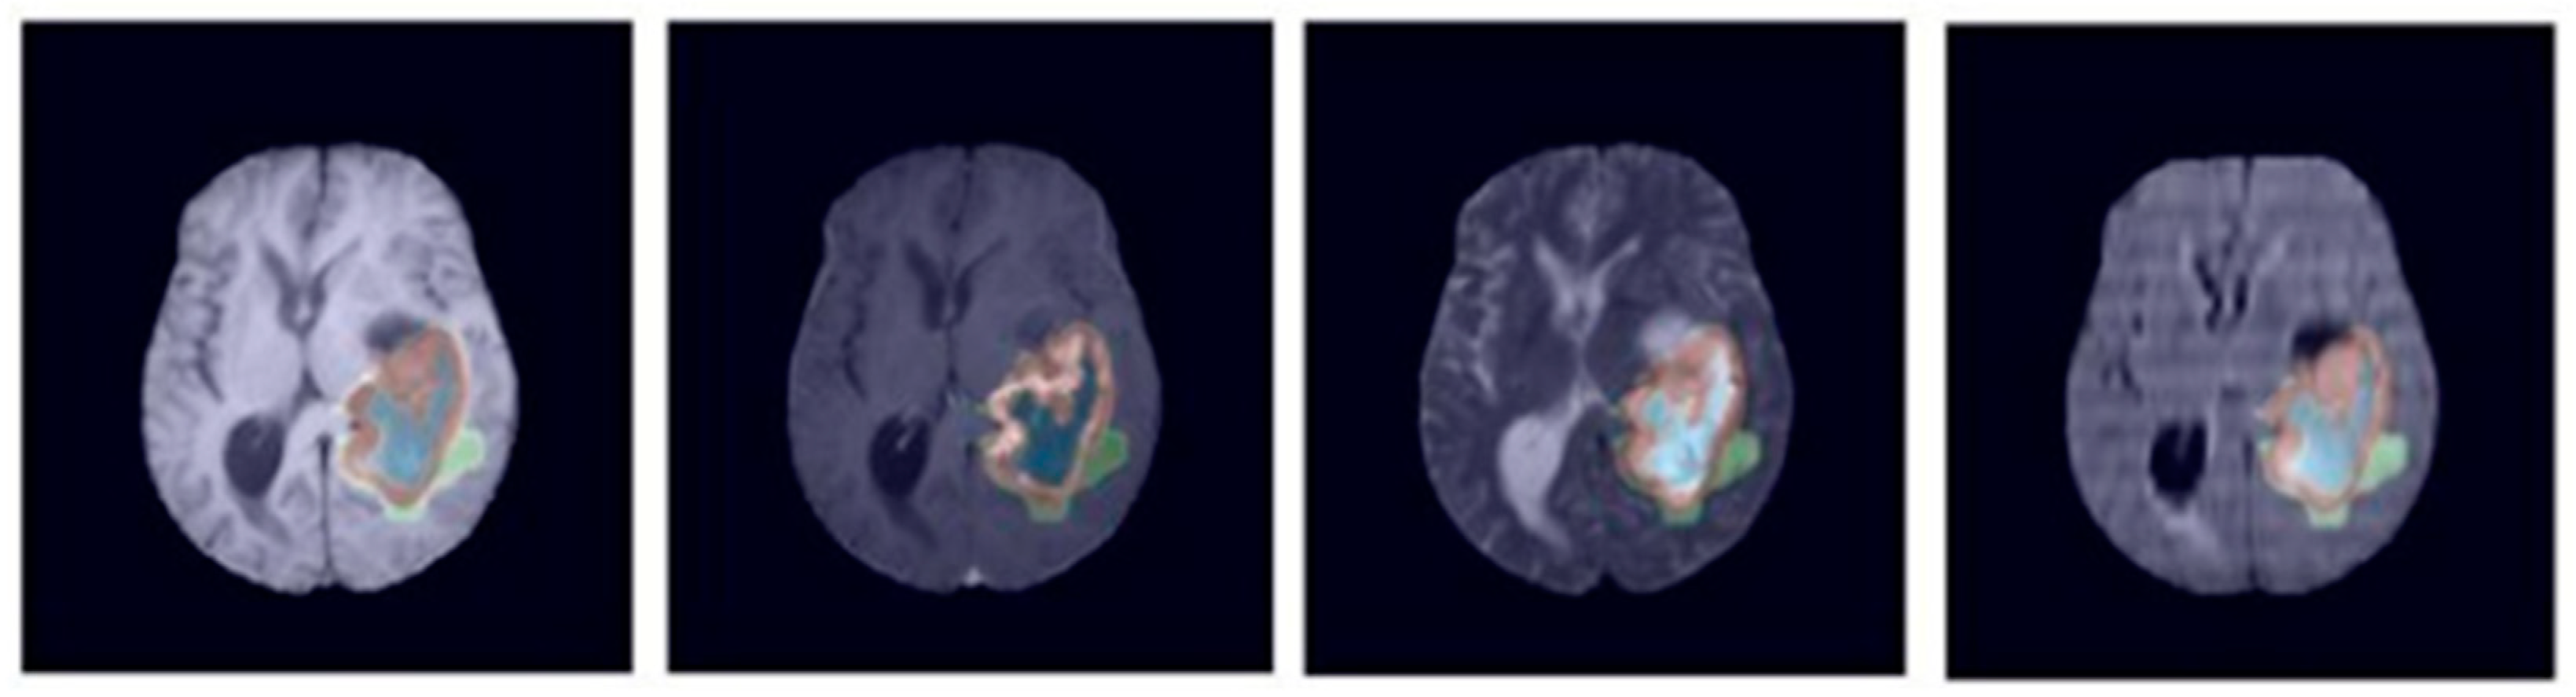

The data are collected from the MRIs of benchmark datasets: BraTS 2019 (https://www.kaggle.com/datasets/aryashah2k/brain-tumor-segmentation-brats-2019, accessed on 1 June 2024), BraTS 2020 (https://www.kaggle.com/datasets/awsaf49/brats20-dataset-training-validation, accessed on 1 June 2024), and BraTS 2021 (https://www.kaggle.com/datasets/dschettler8845/brats-2021-task1/code, accessed on 1 June 2024), which consists of the same dataset, but with different training, testing, and validation sets. These datasets consist of 3D scans of MRI with precise types of brain tumor and the same modalities, such as T1, T1-weighted, T2-weighted, T1ce and FLAIR. The BraTS 2021 consists of 1251 training set, 570 testing set and 219 validation sets. The sample MRI scans of BraTS 2021 is depicted in Figure 2.

Figure 2.

Example MRI brain scans of BraTS 2021 database [34].